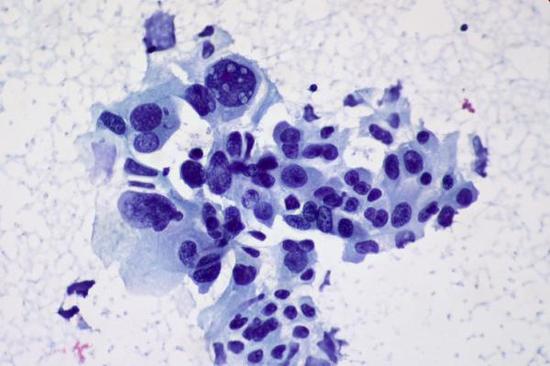

另外一方面,自2003年,“非典”爆发以来,中国的医院都在积极地建立数字化基础设施。这样的趋势,也让推想科技能够使用中国健康数字化记录作为深度学习模型的训练数据。同时,公司还从全国各地20家医院(包括北京协和医院和上海长征医院)中实时收集数据。有了数据后,利用深度学习算法可以提高识别准确率,还能诊断出一些人眼无法看出的细微病变。

前期,我们主要是集中在胸部的肺、心脏等方面的疾病。”陈宽说,“现在随着产品逐渐成熟,迭代速度不断加快,我们在向头部、腹部、股骨头、病理、超声等领域扩展。”

在2013年,自动识别疾病,提高医院诊断的深度学习方法就被《MIT科技评论》评为当年的十大技术突破之一。据《MIT科技评论》报道,利用深度学习算法模型进行医学诊断在美国的医疗机构越来越流行。目前,深度学习算法在治疗皮肤癌上已经可以比肩专业医生;在通过视网膜图像诊断常见失明原因上也有所成就。